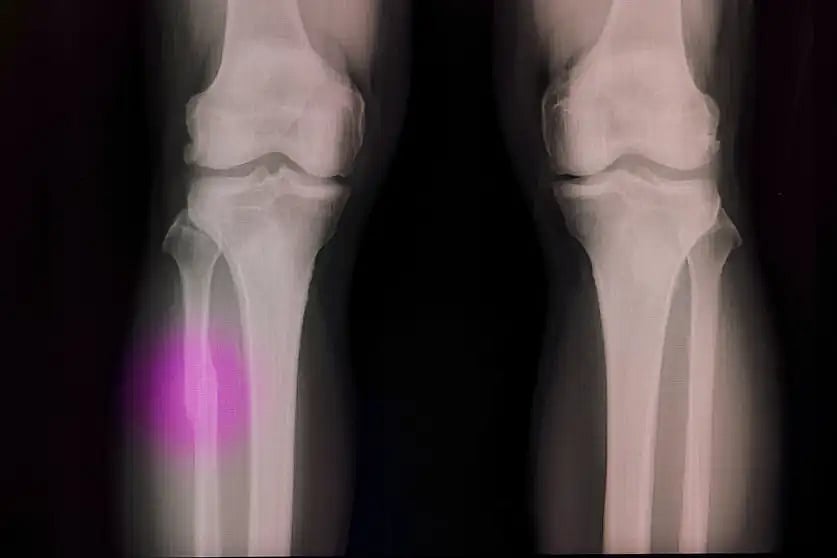

খেলাধুলা করতে গিয়ে হাত-পা ভাঙেনি, এমন দুরন্ত কিশোর খুব কম আছে। তুমি কোন দলে? কয়েক দিন আগেও তোমার পা মচকে গেছে! ভারী দুঃখের কথা। কিন্তু তুমি নিশ্চয়ই জানো, হাড় ভাঙা মানেই প্লাস্টার, অস্ত্রোপচার আর মাসের পর মাস বিছানায় পড়ে থাকা। কখনো কখনো ভাঙা হাড় জোড়া লাগাতে মেটাল স্ক্রু বা পাতের দরকার হয়। এটা তো ভীষণ যন্ত্রণাদায়ক। তবে বিজ্ঞানীরা এবার এমন এক জাদুকরি সমাধান এনেছেন, যা শুনলে তুমি অবাক হবে।

অস্ট্রেলিয়ার একদল গবেষক তৈরি করেছেন বিশেষ ধরনের জৈব আঠা। এই আঠা ব্যবহারের জন্য তাঁরা বানিয়েছেন থ্রি-ডি প্রিন্টিং কলম বা গ্লু গান। এই কলম দিয়ে ভাঙা হাড়ের জায়গায় বিশেষ জেল বা আঠা লাগিয়ে দেওয়া হয়। এরপর সেখানে অতিবেগুনি রশ্মি বা বিশেষ আলো ফেললেই সেই আঠা শক্ত হয়ে হাড়ের মতো মজবুত হয়ে যায়!

এই প্রযুক্তির নাম দেওয়া হয়েছে বায়োপেন। এটি ব্যবহার করলে হাড় জোড়া লাগতে সময় কম লাগবে এবং রোগীকে প্লাস্টারের যন্ত্রণা সহ্য করতে হবে না। চিকিৎসকেরা এখন অপারেশনের টেবিলে বসেই এই কলম দিয়ে ভাঙা হাড় নিখুঁতভাবে জোড়া লাগিয়ে দিতে পারবেন। বিজ্ঞানের কল্যাণে হয়তো ভবিষ্যতে প্লাস্টার করা বিষয়টা জাদুঘরেই চলে যাবে!